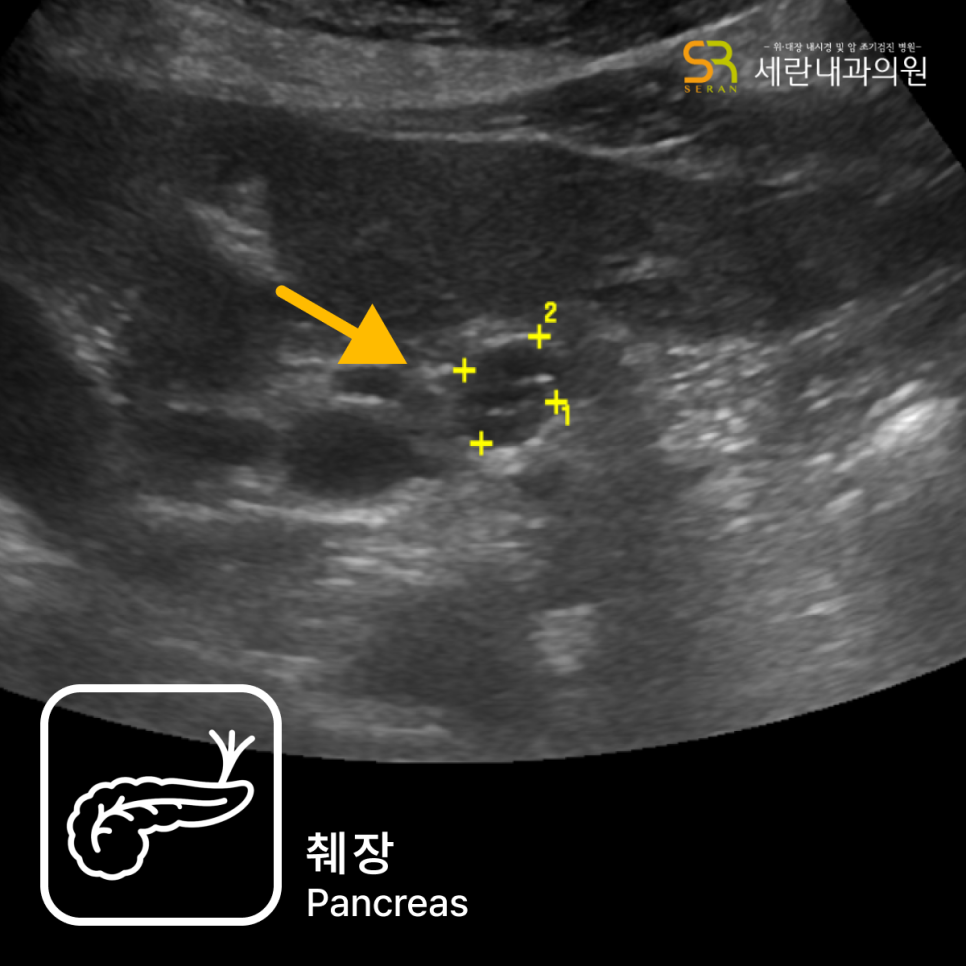

조기 위암 및 고위험 병변

표면이 거칠거나 궤양을 동반한 평평한 병변, 주변 점막과 색이 다른 부위 등은 조기 위암 가능성이 있어 정확한 위치 표시와 충분한 조직검사가 필요합니다. 조직 결과에 따라 내시경 절제술로 치료가 가능한지, 수술이 필요한지 결정하게 됩니다.

내시경 결과는 조직검사 소견, 환자의 증상, 나이, 가족력과 함께 종합적으로 해석합니다. 의료진은 결과를 바탕으로 약물치료 기간, 헬리코박터 제균 여부, 추적 내시경 시기와 생활습관 교정 방향까지 함께 안내하게 됩니다.